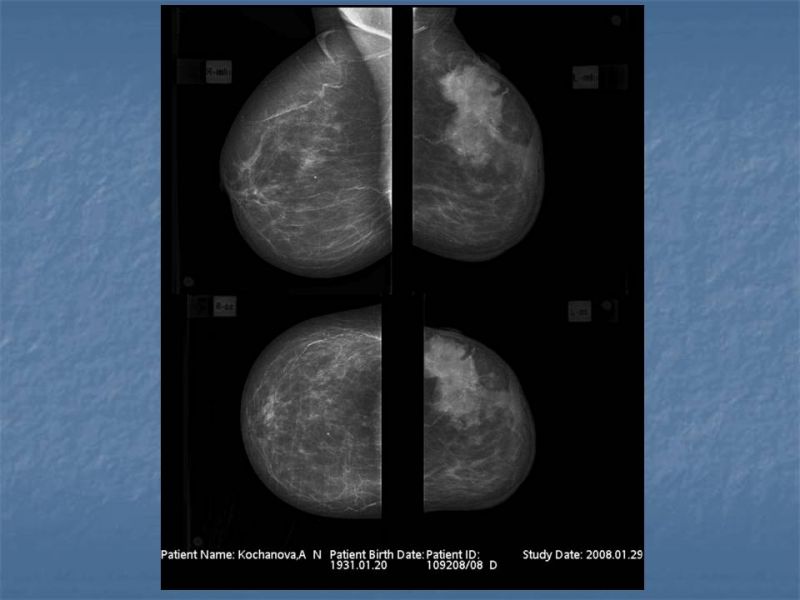

При отсутствии жалоб проходить УЗИ необходимо пациенткам возрастом 25–39 лет один раз в два года, старше 40 — ежегодно. УЗИ молочных желез после 40 лет важно проводить регулярно с целью профилактики онкологических заболеваний. Гормональные изменения, связанные с возрастными процессами, повышают риск появления новообразований.

Кому противопоказано

УЗИ практически не имеет противопоказаний. Однако важно отметить, что информативность обследования груди таким способом у женщин молодого возраста выше, поскольку ткани молочных желез с возрастом становятся более рыхлыми. Поэтому после 40 лет УЗИ в большинстве случаев сочетается с рентген-диагностикой (маммографией).